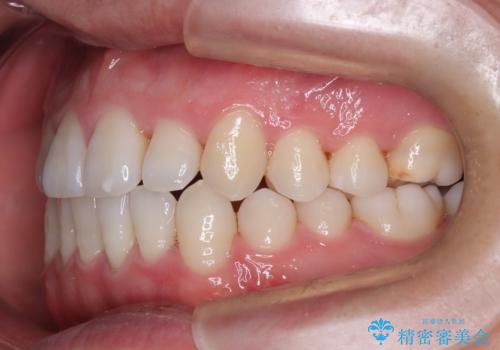

- 前歯のすきっ歯が気になると来院された患者様です。

前歯の隙間をマウスピース矯正(インビザライン)を使用して、閉じていきました。